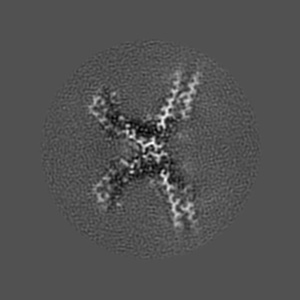

CTE typeIII tau filament

Helical reconstruction2.7 Å

Tau filaments from amyotrophic lateral sclerosis/parkinsonism-dementia complex adopt the CTE fold.